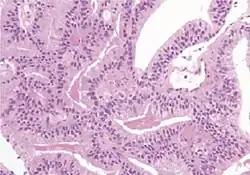

| Pseudohyperplastic carcinoma | 2%[5] | 11%[5] |

|

Tumorous glands: | 3+3=6[1] | ||